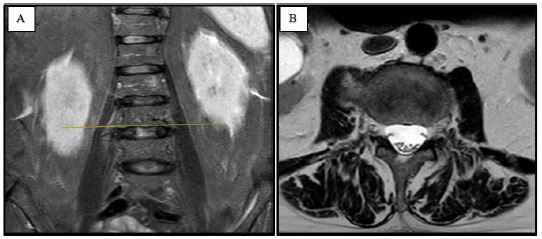

The bony spur was carefully drilled away, and an X-ray was performed to confirm the complete removal of the osteophyte (Figure 3B & C).

Figure 3: Lumbar X-ray imaging displaying lumbar tract before (A) and after the osteophyte’s drilling (B,C).